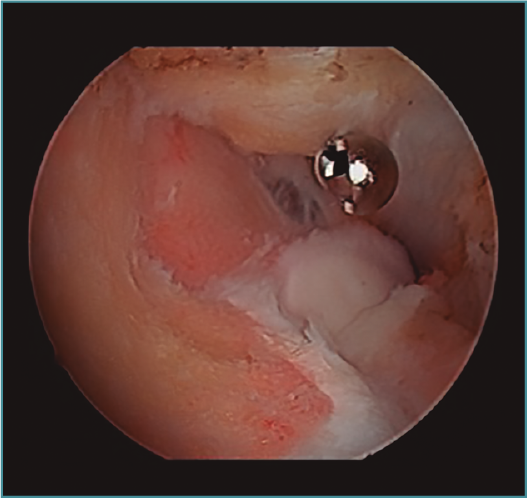

Acto seguido, realizamos nuestra secuencia de trabajo descrita anteriormente (visualización, creación de espacio, trabajo óseo y trabajo de partes blandas). El fresado óseo debe realizarse siempre con el instrumental motorizado orientado hacia el húmero, para evitar las lesiones de partes blandas. El uso de fresas o el sinoviotomo en modo no oscilante y a alta velocidad nos permitirá eliminar los osteofitos que interfieran con la movilidad, especialmente aquellos que ocupan la fosa radial o coronoidea (Figura 8). También es frecuente tener que eliminar osteofitos que aumentan la altura de la coronoides (Figura 9). Una vez eliminado el material óseo (Figura 10), flexionamos el codo para comprobar el aumento de flexión conseguido, que no será completo hasta que liberemos la cápsula posterior y la banda posterior del ligamento colateral medial. Como último paso en la cámara anterior, procedemos a la eliminación de la cápsula articular. Introducimos un Basket recto desde el portal anteromedial y vamos mordiendo la cápsula, atrapándola, cortándola y realizando un movimiento de batido hacia proximal para separar el fragmento capsular de las partes blandas anteriores. Progresamos lateralmente, descubriendo el vientre muscular del braquial anterior, hasta que aparezca tejido graso detrás de la cápsula resecada. En este momento, cambiamos los portales y miramos desde el portal anteromedial proximal y utilizamos la pinza Basket desde el portal anterolateral. Una vez realizada esta capsulotomía amplia, usamos el sinoviotomo para eliminar los restos capsulares proximales. Durante todo este proceso, utilizamos un retractor desde el portal anterolateral proximal para tensar la cápsula y proteger, sobre todo, el nervio radial, que queda situado justo en la grasa lateral al músculo braquial y anterior a la cabeza del radio, y a escasos milímetros de nuestro instrumental de trabajo; aunque no es aconsejable, es posible traccionar de él e introducirlo en la articulación con ayuda de un palpador introducido en la grasa que lo recubre. El nervio mediano se encuentra medial al músculo braquial, pero en un plano bastante más anterior, lo cual hace que esté mucho más protegido(12,13).

Figura 8. Osteofitos ocupando la fosa radial y coronoidea, observados desde el portal anteromedial proximal.

Figura 9. Osteofito coronoideo observado desde el portal anterolateral.

Figura 10. Mismo caso que en las Figuras 8 y 9 después del trabajo óseo. Obsérvese la recreación y fusión de ambas fosas radial y coronoidea con el típico aspecto de “tobogán” después del fresado de la cara anterior del húmero y la disminución de la altura de la coronoides. Todavía no se ha procedido a realizar la capsulectomía.